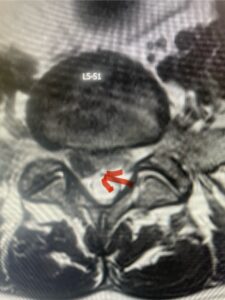

Fig 1b: Note the left L2-3 facet joint (blue arrow) is normal in size compared to the right (red arrow)

In this next case, this patient is a 47 year-old female who presents with intractable low back pain with severe pain, numbness, and weakness in the right lower extremity that had gotten progressively worse over a year. The patient had failed conservative management including physical therapy and epidurals. She was noted to have ⅘ weakness of plantar flexion. MRI demonstrated a large right L5-S1 disc herniation with severe compression of the descending right S1 nerve root (Fig 3). It was decided to perform a right L5-S1 hemilaminectomy for removal of the disc fragment and decompress the S1 nerve root. When you expose the disc, one must be certain to release any anterior adhesions to the nerve root in order to prevent a dural tear during retraction of the nerve root. It is also important to make sure during exposure and you finally encounter the dura after removing the ligamentum and fat, to make sure you are looking at the nerve root and not the main trunk of the thecal sac because if you don’t you can avulse or damage the nerve root if you retract the wrong structure.

Fig. 3a: Sagittal and axial T2-weighted lumbar MRI images demonstrating large right L5-S1 disc herniation (red arrows)